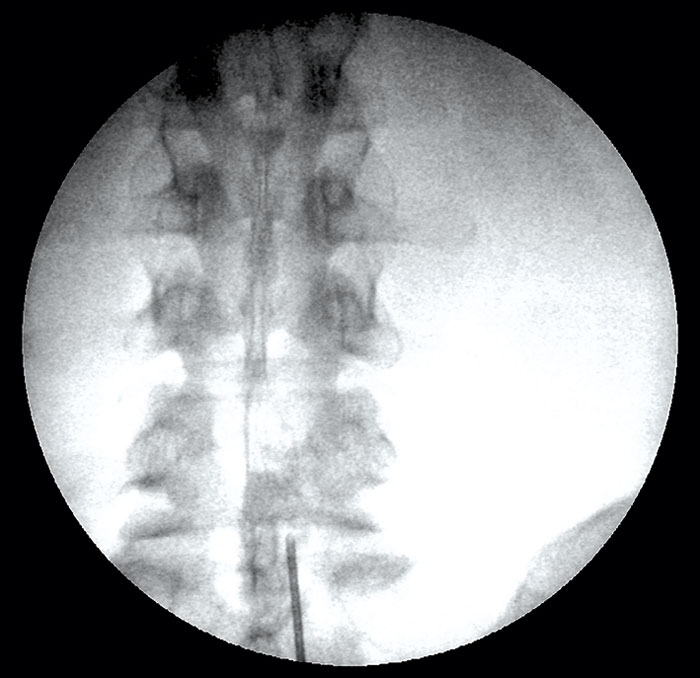

• Alla interlaminära injektioner av steroider ska föregås av röntgenkontroll där nålspetsens placering kontrolleras. Enbart i de fall en patient har dokumenterade kontraindikationer mot kontrastmedel är det acceptabelt att underlåta att använda kontrastinjektion som del i kontrollen av nålens placering (Figur 3). Vid interlaminära injektioner är det acceptabelt att använda steroider i kristallform, exempelvis metylprednisolon.

Figur 3. Röntgenkontroll vid interlaminär injektion.